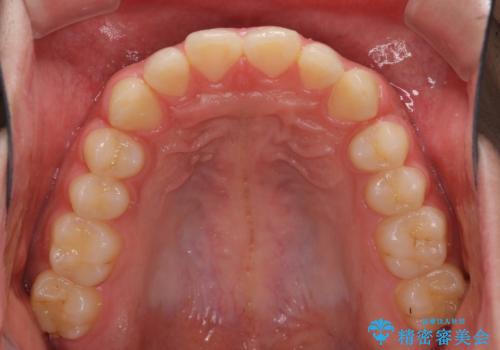

インビザラインによる、すきっ歯の改善

- 前歯がすきっ歯であることを気にして来院された患者様です。

下の前歯がほとんど隠れてしまうくらいの深い咬み合わせであったので、インビザラインを用いて、咬み合わせの高さを改善しながら隙間を閉じていくこととしました。

咬合力で上の前歯が前方に押し出されるようにして隙間ができていましたが、矯正治療により全て閉じることができました。

深い咬み合わせも多少改善され、隙間も閉じたことで、前方に出ていた前歯が引っ込んだため、口も閉じやすくなったとのことでした。